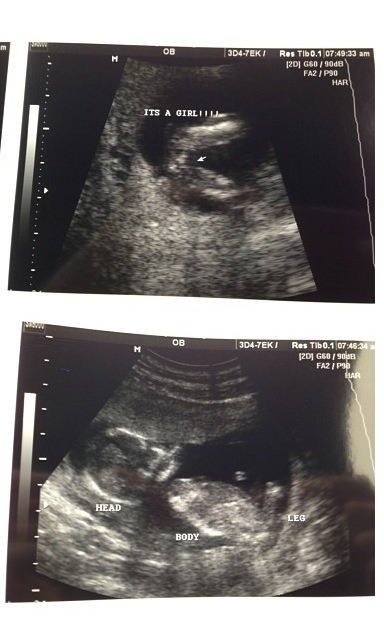

My insurance didn't cover an nt scan but I was looking up 11 week ultrasounds and comparing them to mine does my baby's look normal? I'm being a worry wart :(Attachment 12664

Meaning the nuchal fold I know you can't measure it but in some I found on google it's very obvious

She said everything looked great but I do not remember her measuring the fold. I have a 14 week scan where I think I see the nasal bone but I'm not 100% sureAttachment 12667